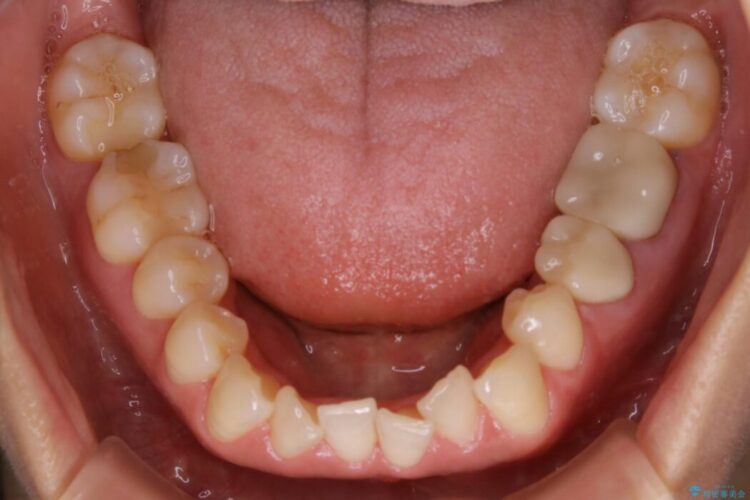

検査したところ歯の叢生自体は歯列幅の拡大やディスキング(IPR)で解決できる範囲内でした。

生えている歯に対して顎の骨が小さいなどでスペースが足りないため舌側へ倒れてしまったり、歯列からはみ出てしまうことがあります。

歯列幅の狭窄の場合は歯列弓を拡大するだけでも歯列を整えるだけのスペース確保が可能になる場合があります。